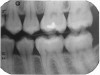

Figure 15 shows bitewings of an 11-year-old boy with high caries risk and history of proximal "kissing lesions" on his primary molars in all four quadrants. He then presented with incipient lesions in his permanent teeth. After resin infiltration (Figure 16), results have been stable for 2 years.

Fig 15. Bitewing of an 11-year-old boy.

Figure 15

Fig 16. Same patient several months later.

Figure 16